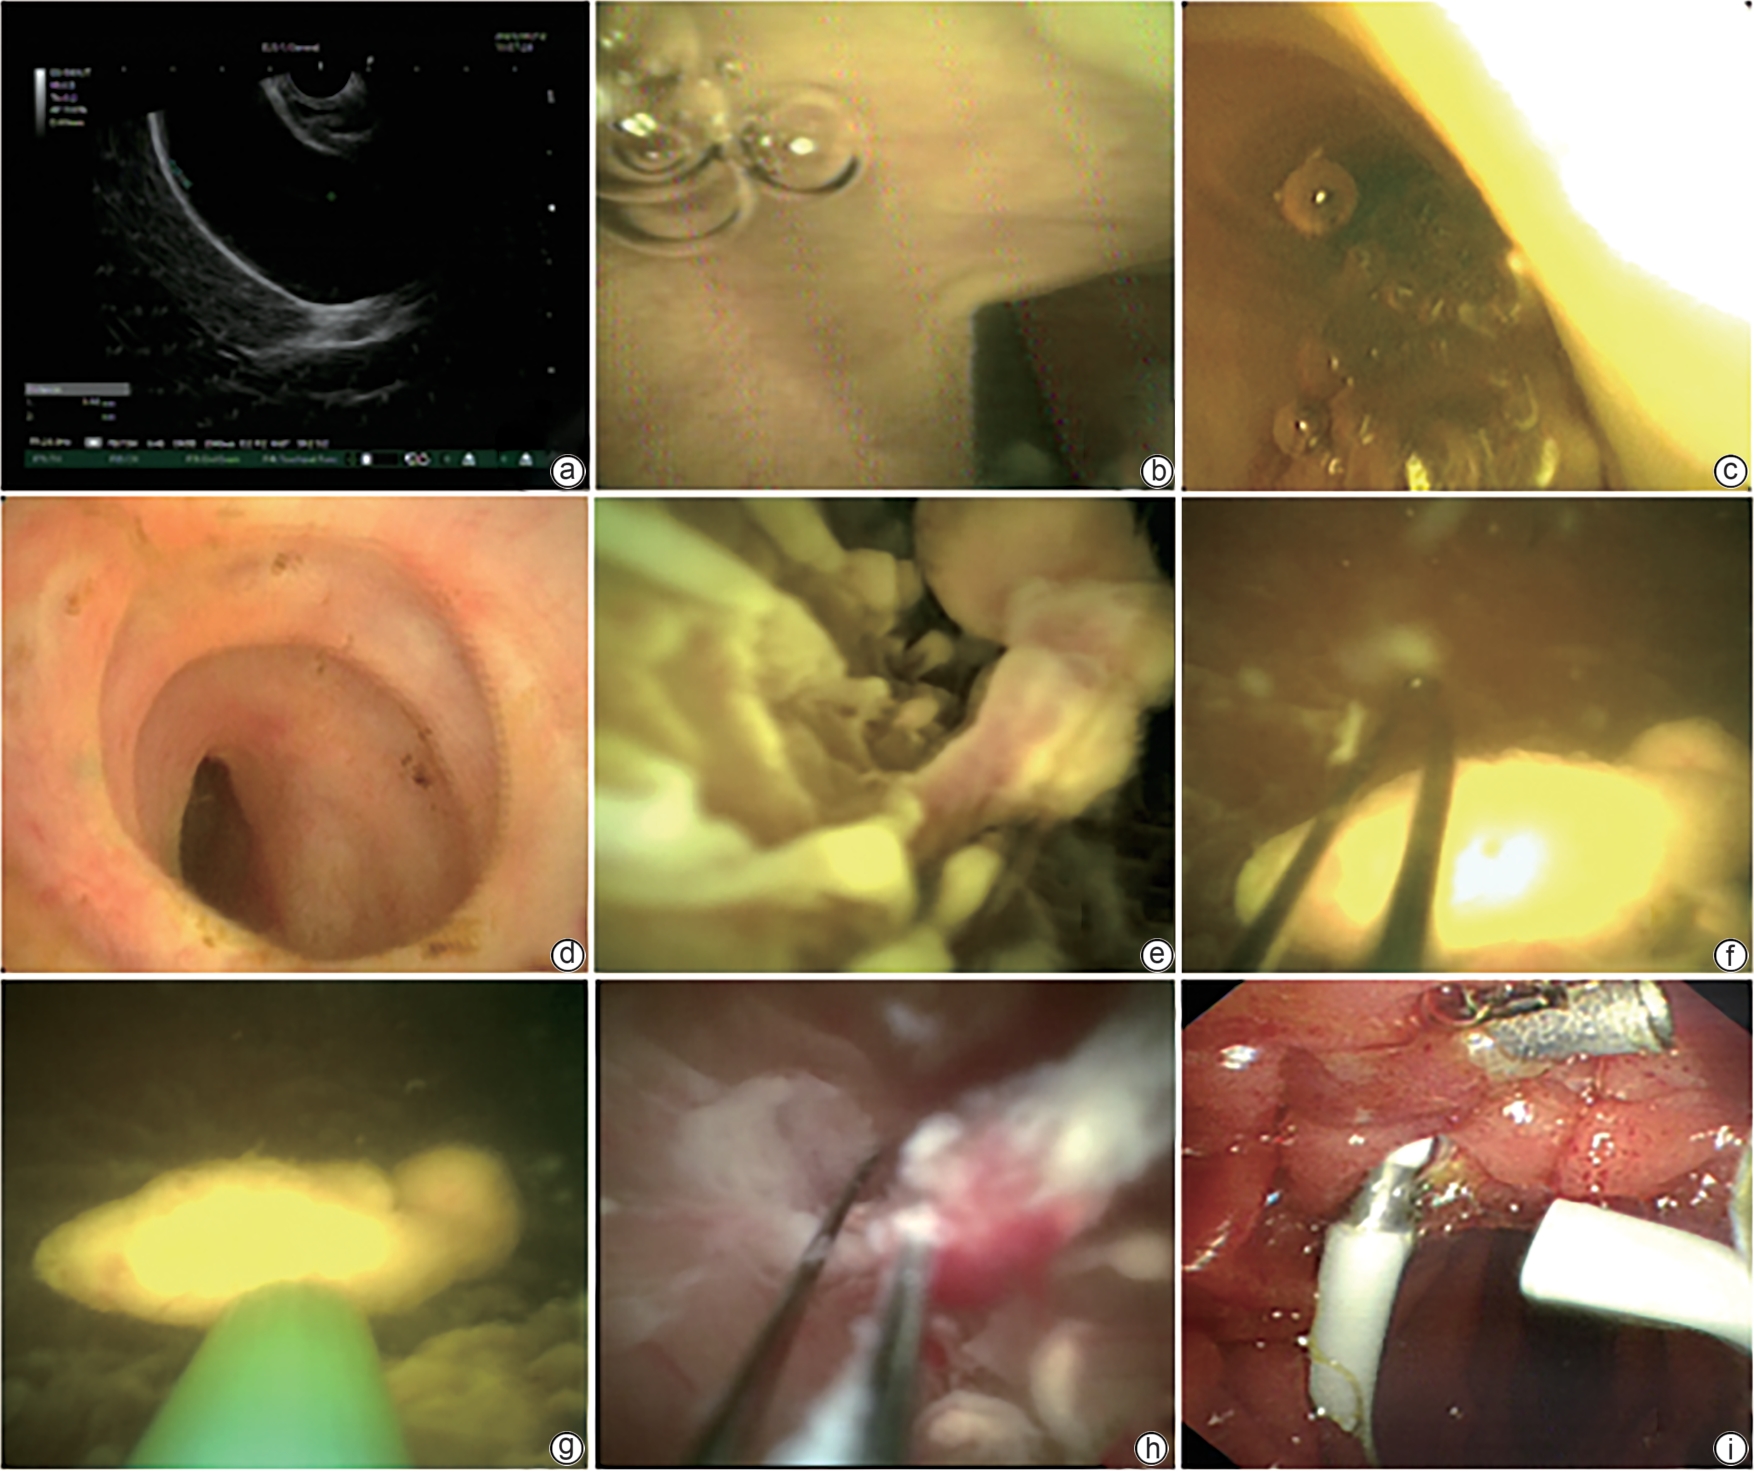

经口胆胰管镜联合内镜逆行胰胆管造影经十二指肠乳头胆囊息肉切除的疗效及安全性分析

陶丽莹, 王宏光, 郭庆梅, 郭享, 朴连玉, 杨沐雨, 于泳, 阮丽斌, 谷建彬, 陈思, 杜迎亭, 盖秀英, 郭思捷

2025, 41(3): 513-517. DOI: 10.12449/JCH250318

摘要(745) HTML (319) PDF (1711KB)(48)

摘要:

目的  探讨通过内镜逆行胰胆管造影(ERCP)联合经口胆胰管镜行经十二指肠乳头胆囊息肉切除治疗的可行性和安全性。  方法  回顾性分析2022年5月—2024年6月于吉林市人民医院消化内镜中心采用ERCP联合经口胆胰管镜行经十二指肠乳头胆囊息肉切除的8例胆总管结石合并胆囊息肉患者的临床资料,收集手术成功率和胆囊息肉清除技术成功率,胆囊管超选方式、整体手术时间、胆囊息肉切除时间、手术并发症等指标。  结果  手术成功率及胆囊息肉切除技术成功率为100%,其中3例患者通过导丝引导直视进入胆囊,5例通过经口胆胰管镜直接进入胆囊;整体手术时间为(51.88±12.34)min,胆囊息肉切除时间为(23.13±10.94)min;胆囊息肉病变直径为2~8 mm;病理结果为3例炎性息肉,1例腺瘤性息肉,4例胆固醇性息肉;术中及术后无并发症,术后随访2~27个月,胆囊无息肉复发。  结论  经口胆胰管镜在内镜下经十二指肠乳头胆囊息肉切除的临床应用,技术上相对安全可行。